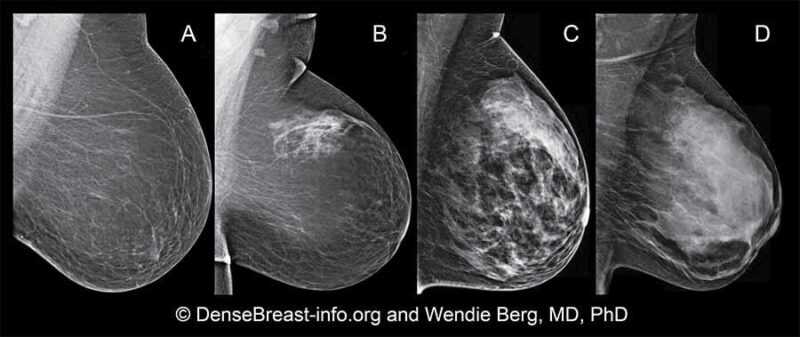

Aún así, la eficacia de las mamografías para detectar anomalías en las mamas es muy alta. La tasa de no detección es del 10% al 15% sobre todo en mujeres con senos densos (senos con más tejido glandular y tejido conjuntivo fibroso que tejido graso) ya que en una mamografía el tejido denso y las anormalidades aparecen iguales como áreas blancas. En ese caso, es necesario hacer pruebas de seguimiento.